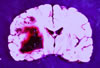

Hemoraji